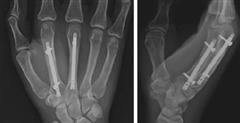

髄内固定

髄内スクリュー固定は、低侵襲性アプローチと良好な転帰に関するエビデンスの増加により、より一般的になっています。中手骨頸部骨折に関する最近のシステマティックレビューでは、順行性髄内固定(髄内スクリューが骨折の近位端に挿入される方法)は、保存的治療や逆行性髄内固定と比較して、より迅速な疼痛軽減と機能改善をもたらすことが報告されています。しかしながら、順行性髄内固定は、インプラントの移動や神経学的合併症のリスクが高くなる可能性があります。逆行性挿入法(髄内スクリューが骨折の遠位端に挿入される方法)は、良好な成績が報告されている新しい手技です。中手骨頭骨折では、遠位骨片の大きさが、髄内スクリューによる順行性固定において問題となる場合があります。逆行性挿入法は、遠位骨片をより確実に捕捉できるため、一部の外科医は、これをより簡便な手技であると述べています。

文献1】より